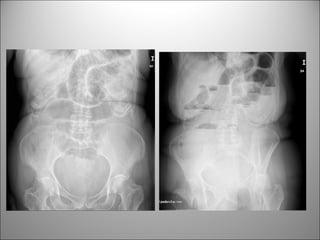

ÍLEO

• NIVELES PER SE NO INDICAN OBSTRUCCIÓN

• AUSENCIA DE NIVELES NO DESCARTA ÍLEO

NEUMOPERITONEO

• Signo de la doble paréd

VOLVULUS